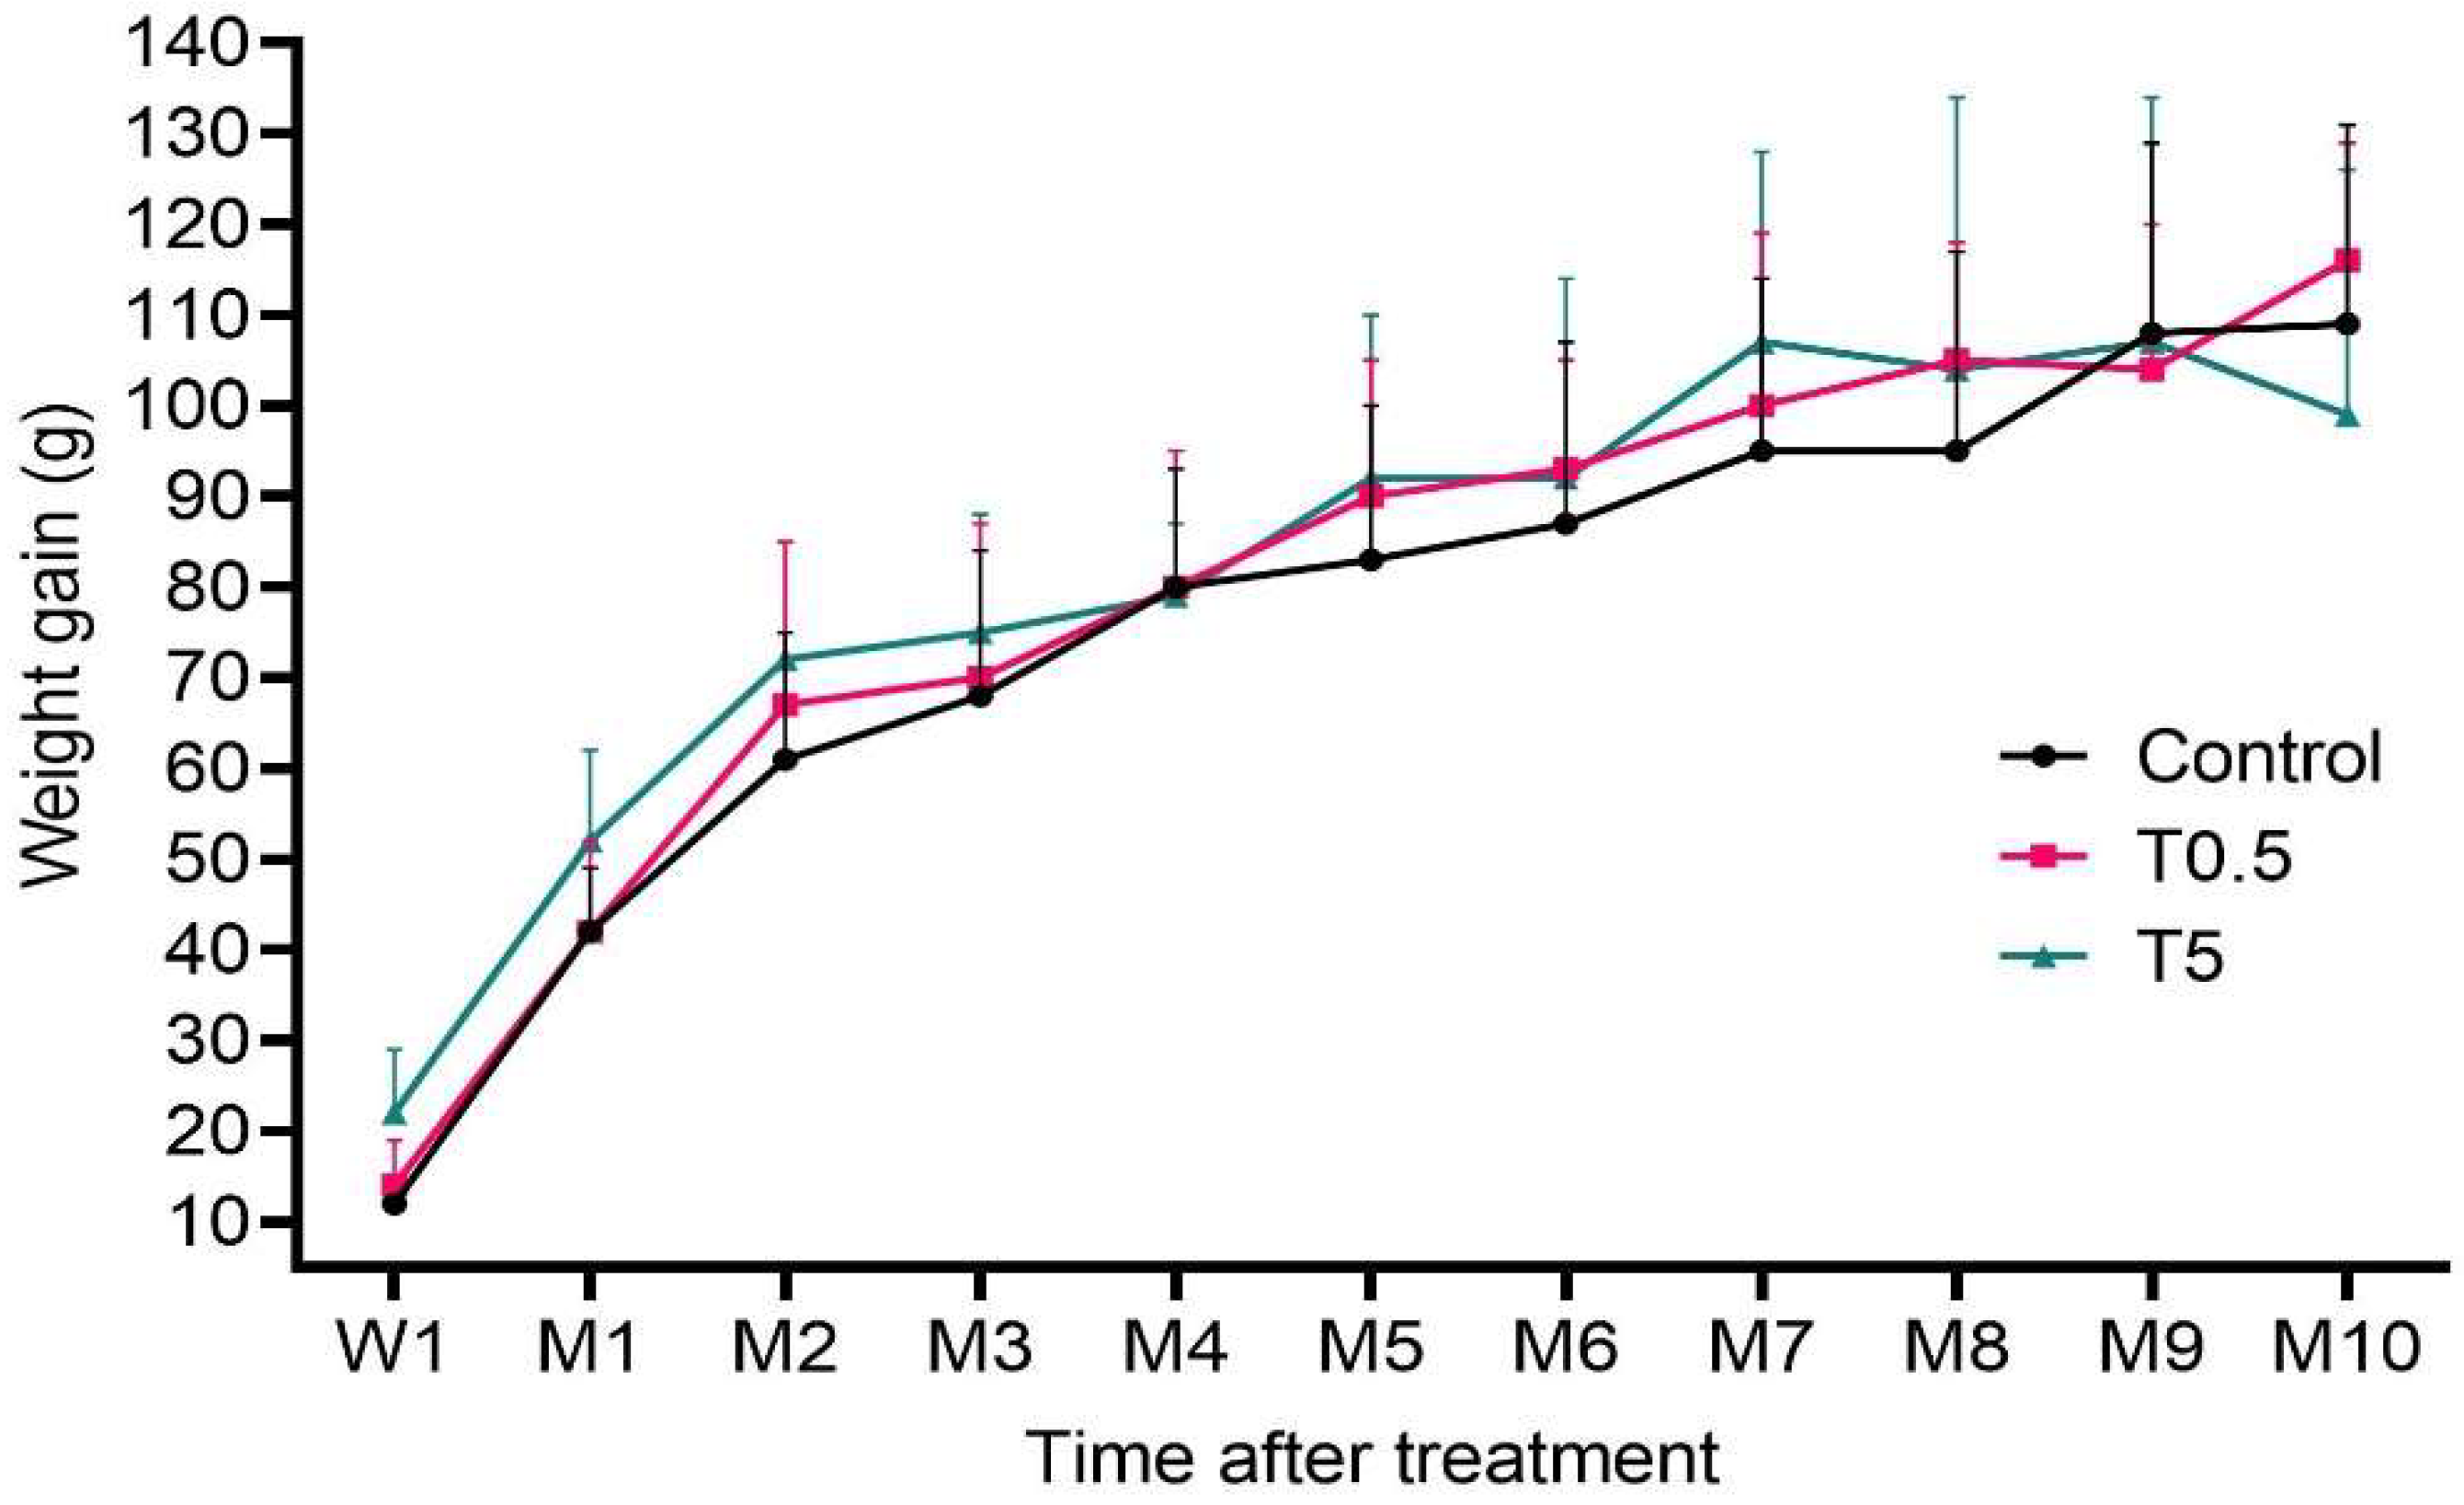

3.2. Clinical, Hematological, and Biochemical Analysis

3.5. DMSA-MNP Detection in the Organs